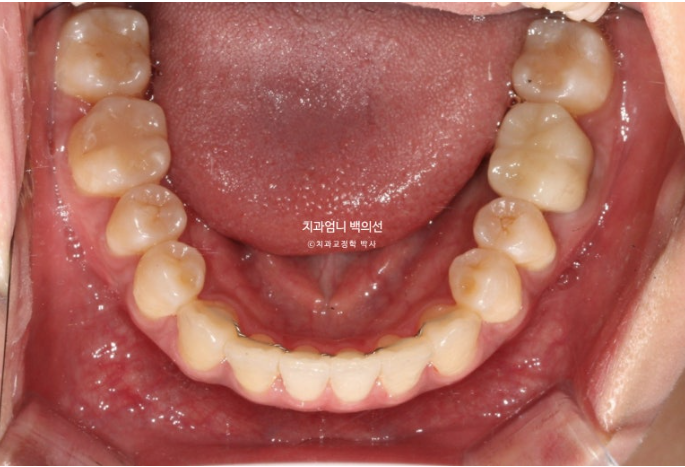

아래는 사랑니가 있던 공간으로 어금니를 뒤로 밀어내어 최종적으로 아래 앞니가 뒤로 2mm 들어가도록 했습니다.

아래 앞니가 사랑니 공간을 이용하여 뒤로 2mm 후방이동 했습니다.

앞니 반대교합과 절단교합이 해소가 되며 아랫입술 역시 뒤로 2mm 들어갔습니다.

위 앞니는 목표대로 앞으로 나오지 않게 치료가 잘 되어 윗입술은 변화가 없습니다.